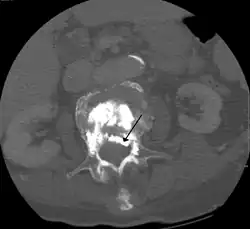

Some of the associated risks are from the leak of acrylic cement to outside of the vertebral body. Although severe complications are extremely rare, infection, bleeding, numbness, tingling, headache, and paralysis may ensue because of misplacement of the needle or cement. This particular risk is decreased by the use of X-ray or other radiological imaging to ensure proper placement of the cement.[2] In those who have fractures due to cancer, the risk of serious adverse events appears to be greater at 2%.[23]